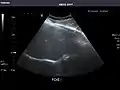

Spleen

Spleen: Normal in size.